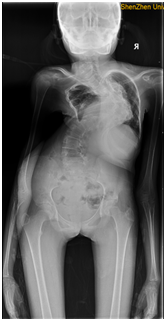

鄒女士手術前影像圖

合併II型呼吸衰竭重度脊柱側彎、雙側髖關節僵直的摺疊人、合併腦癱的極重度脊柱側彎等多位患者在獲得治療後已自信回歸正常生活。今年32歲的鄒女士(化名)曾經差點放棄治療,她是II型呼吸衰竭的極重度脊柱側彎患者(FEV1(%)=17.5,BMI=12.9),手術風險極高,在陶惠人教授的堅持和專業治療下,手術順利且恢復良好,術後22個月的時候,鄒女士順利生育,母子平安。